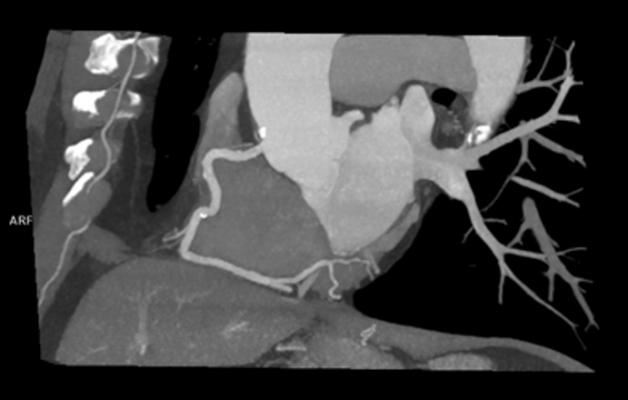

CCTA is a contrast-enhanced radiographic assessment of the coronary arteries. It is a non-invasive alternative that can show narrowed or blocked blood vessels. Although CCTA has been endorsed by several guidelines from the American College of Cardiology/American Heart Association, CCTA has been slow to be adopted for low- to intermediate-risk chest pain patients. Through its Centers of Excellence, Mednax works to leverage such best-practice programs across its national network and expand services and technology nationwide to provide better and faster care for patients.